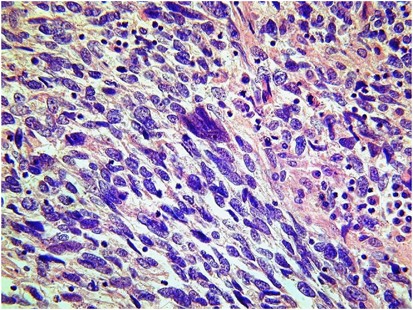

Histologically, the mixed nature of the tumour is exemplified by the presence of both epithelial and stromal elements, the latter predominating. At low power magnification, the tumour often has a phyllodes-like (leaf-like or club-like) architecture (Figure 7). The epithelial elements usually consist of glands, which may be dilated or slit-like with a phyllodes-like appearance, lined by cuboidal or low columnar cells. In most cases, the epithelium is endometrioid and resembles proliferative endometrium, although ciliated, mucinous and squamous epithelium may also be seen. Uncommonly, the epithelial component exhibits glandular complexity resembling atypical hyperplasia/endometrial intraepithelial neoplasia or carcinoma. The latter is usually a low-grade endometrioid carcinoma.28 The stromal component, which is typically low grade, is composed of spindled and/or round cells with scant cytoplasm, but rarely can be high grade. Intraglandular protrusions of stroma and the manner in which the stromal cells, which often resemble endometrial stromal cells, concentrate around or beneath the glandular elements (‘periglandular cuffing’) are characteristic (Figure 8). The ‘cuffing’ may be very thin (and thus overlooked) but is where nuclear atypia and mitotic activity are typically found (Figure 9). Although a mitotic rate of ≥2 per 10 high power fields (HPFs) is often seen, some tumours have a lower mitotic rate and should be diagnosed as adenosarcoma if the tumour has the characteristic aforementioned features as reflected in the 2014 WHO classification.1